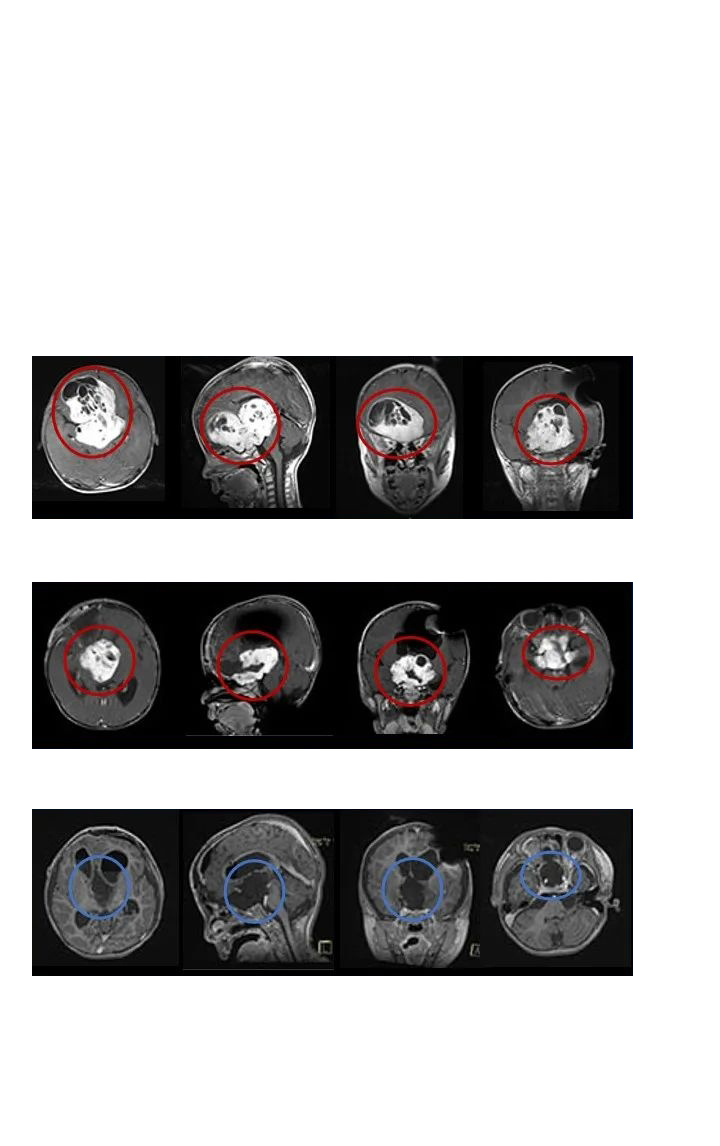

毛細胞型星形細胞瘤是一種預(yù)后較好的低級別膠質(zhì)瘤,不管發(fā)病位置在哪里,手術(shù)全切基本可達到不復(fù)發(fā)的更好效果。在治療中,一次手術(shù)尤為重要,應(yīng)在不損傷患者正常腦組織和功...

INC國際教授毛細胞型星形細胞瘤疑難手術(shù)案例

毛細胞型星形細胞瘤是一種預(yù)后較好的低級別膠質(zhì)瘤,不管發(fā)病位置在哪里,手術(shù)全切基本可達到不復(fù)發(fā)的更好效果。在治療中,一次手術(shù)尤為重要,應(yīng)在不損傷患者正常腦組織和功能神經(jīng)的前提下切除腫瘤,避免復(fù)發(fā)和后遺癥,更大水平好轉(zhuǎn)患者術(shù)后生存質(zhì)量。

另外,鑒于一些腫瘤病發(fā)部位位置較深,解剖結(jié)構(gòu)復(fù)雜,選擇醫(yī)術(shù)、有成功手術(shù)經(jīng)驗的醫(yī)生主刀手術(shù)可更大水平實現(xiàn)保神經(jīng)、保功能、全切腫瘤、無殘留的手術(shù)效果。INC國際神經(jīng)外科醫(yī)生致力國內(nèi)外醫(yī)術(shù)學(xué)術(shù)交流、加強疑難病癥救治,其旗下國際神經(jīng)外科顧問團(World Advisory Neurosurgical Group,WANG)是由國際各發(fā)達國家神經(jīng)外科各亞??浦飨?、宗師級聯(lián)合組成的教授組織,包括以年輕時即是疑難手術(shù)入路重要奠基者、以超群的手術(shù)技術(shù)救治超過40個國家疑難病癥患者的國際神經(jīng)外科聯(lián)合會(WFNS)教育委員會主席Bertalanffy巴特朗菲教授;擅長小兒腦瘤和癲癇治療的兒童神經(jīng)外科專家James T. Rutka教授;十幾位教授們不僅擁有高超的手術(shù)技巧和豐富的臨床經(jīng)驗,還較為重視患者細致神經(jīng)功能的康復(fù),以期提升其生活質(zhì)量、生存預(yù)后。有需者可電話400-029-0925詳細垂詢學(xué)術(shù)交流、遠程咨詢、聯(lián)合咨詢或教授主刀等。